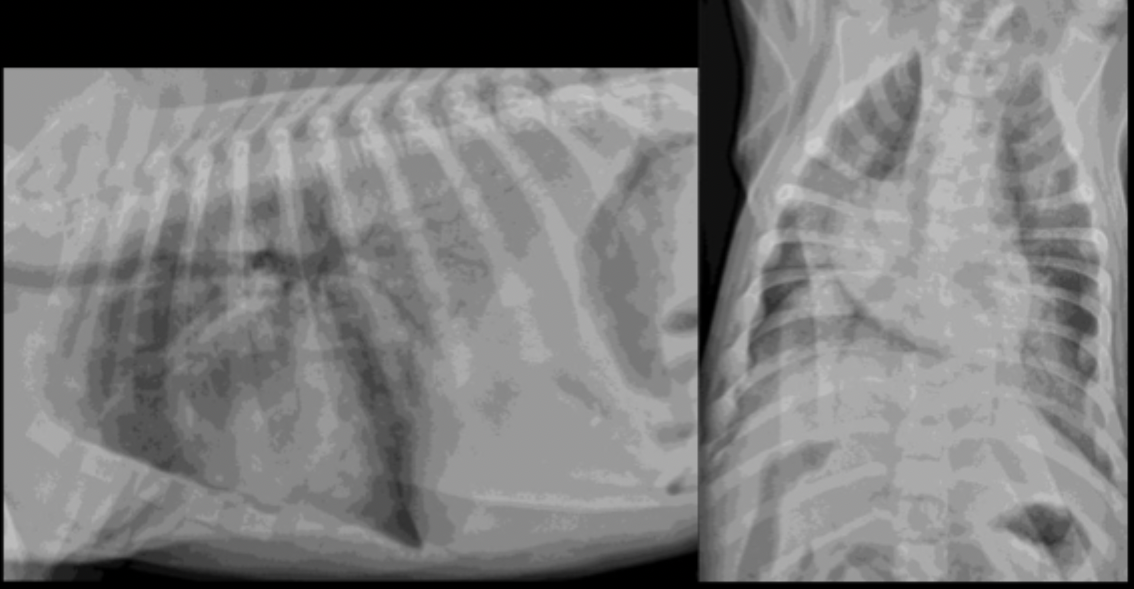

What can be seen on these feline radiographs?

left atrial enlargement

What pulmonary pattern can be seen in this radiograph?

diffuse interstitial pattern

What pattern does feline cardiogenic edema generally present as?

random

patchy

peri-vascular in distribution